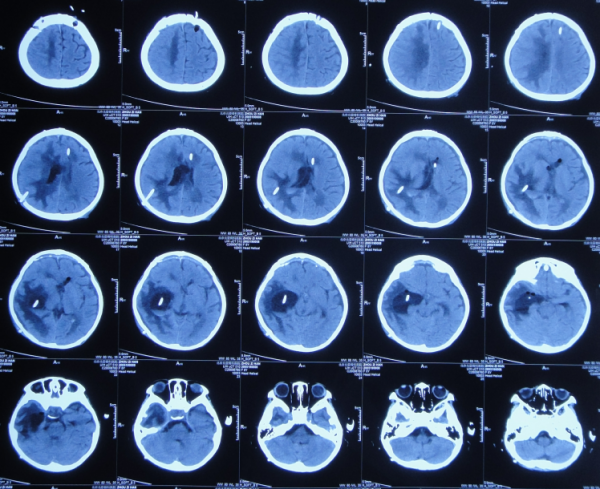

腦室外引流術後次日即2019年12月7日,查頭部CT示腦室出血,引流術後狀態(圖-3)。

圖-3:2019年12月7日頭部CT

引流術後3天即2019年12月9日,再次查頭部增強CT掃描示胺區腫瘤(圖-4)。

圖-4:2019年12月9日頭部增強CT